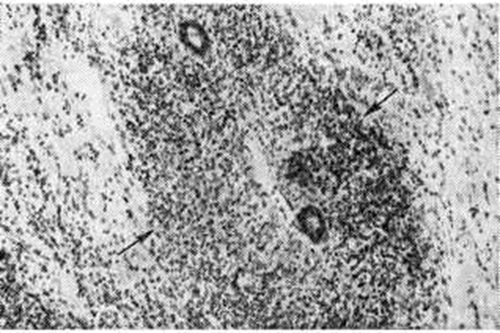

Параллельно с гранулематозным процессом происходит повреждение окружающих тканей, что проявляется развитием в них дистрофических и некротических изменений. В дальнейшем наступает лизис некротизированных элементов с замещением их сначала лимфоидными клетками, которые при благоприятном течении заболевания вытесняются фибробластами и рубцовой тканью. Интенсивность дистрофических и некротических изменений в тканях зависит от характера гранулематозного процесса. При преобладании фиброзирующихся небольших гранулем дистрофические изменения в окружающих тканях обычно незначительны. При преобладании обширных гранулем с диффузной лимфоидноклеточной инфильтрацией межуточной ткани выражены некротические изменения. При этом в процесс вовлекаются мелкие сосуды с развитием в них васкулита (смотри полный свод знаний) и фибриноидного некроза стенки. Как и при других системных заболеваниях, при Саркоидоз выявляют изменения в различных органах. Во внутренних органах поражения локализуются преимущественно в лёгких и бронхах, а также в печени, сердце, почках. При длительном хронический течении Саркоидоз поражение лёгких нередко заканчивается фиброзом межальвеолярных перегородок и перестройкой сосудов, свидетельствующей о развитии лёгочной гипертензии. В редких случаях острого течения Саркоидоз обнаруживается тяжёлое поражение лёгких с развитием гранулем в межальвеолярных перегородках и явлениями гранулематозного васкулита. Так называемый гранулематозный гепатит проявляется развитием характерных гранулем в паренхиме и междольковых прослойках печени. Поражение сердца встречается довольно редко, оно может обусловливать тяжёлое клинические, течение болезни и быть причиной внезапной смерти. При морфологический исследовании в этих случаях выявляют гранулематозный миокардит (рисунок 3), деструкцию сосудов, повреждение кардиомиоцитов. В почках гранулемы чаще локализуются в корковом веществе. При этом в капиллярах почечных клубочков патологический процесс развивается по типу гранулематозного гломерулонефрита. При поражении глаз гранулемы образуются в тканях сосудистой оболочки, сетчатки, зрительного нерва, наблюдается картина узелкового иридоциклита (смотри полный свод знаний) и хориоретинита (смотри полный свод знаний: Хориоидит). Нередко обнаруживается ретинальный перифлебит, отмечается гнойное воспаление цилиарного (ресничного) тела с экссудатом вокруг его отростков и абсцессом в стекловидном теле. При Саркоидоз кожи гранулемы обычно располагаются в средних и глубоких слоях дермы. Поражения центральная нервная система, костей, суставов и скелетных мышц описаны ниже, в клинические, картине заболевания. Клиническая картина. В СССР получила распространение классификация Саркоидоз, предложенная А. Е. Рябухиным и соавторами (1975), в которой учтены достоинства ряда других классификаций, прежде всего широко принятой за рубежом классификации Вурма — Рейнделля — Гейльмейера. По классификации А. Е. Рабухина различают 3 формы Саркоидоз: внутригрудную, внегрудную и генерализованную, при которой торакальные проявления заболевания сочетаются с поражением других органов. В рамках наиболее распространённых (90—98% всех случаев Саркоидоз) генерализованной и внутригрудной форм в зависимости от выраженности и характера рентгеноморфологическое изменений выделяют I, II и III стадии заболевания. I стадия характеризуется поражением лимфатических, узлов грудной полости при отсутствии изменений в лёгких, II и III — поражением ткани лёгких. При этом различают следующие рентгеноморфологическое варианты поражения лёгких. Во II стадии: IIа — интерстициальные изменения, IIб — мелкоочаговые изменения, IIв — средне и крупноочаговые изменения, IIг — конгломерирующие изменения (без фиброза). В III стадии: IIIа — конгломерирующие изменения при наличии фиброза, IIIб — массивный очаговый или диффузный фиброз. Таким образом, II стадия Саркоидоз лёгких отличается от III стадии отсутствием выраженного лёгочного фиброза. Для оценки течения Саркоидоз рекомендуются (независимо от формы заболевания) следующие качественные характеристики: затихание, излечение, обострение, прогрессирование. Кроме того, необходимо учитывать осложнения заболевания как со стороны лёгких, так и других поражённых органов. Некоторые учёные не прибегают к столь детальной классификации рентгеноморфологическое изменений, ограничиваясь выделением внутригрудной лимфожелезистой (I), медиастинально-лёгочной (II) и лёгочной (III) стадий Саркоидоз Клинические, картина Саркоидоз характеризуется значительным разнообразием клинические, проявлений в зависимости от того, какие органы и в какой степени вовлечены в патологический процесс. Кроме того, важное значение имеют возникающие при Саркоидоз спонтанные ремиссии, обострения, а также возможность в части случаев самопроизвольного излечения. Внутригрудная форма Саркоидоз, то есть поражение лимфатических, узлов средостения, бронхов, лёгких, нередко протекает бессимптомно, особенно в начале заболевания, когда лишь случайное рентгенологическое обследование позволяет обнаружить патологический изменения. Клинические, признаки в начальных стадиях заболевания неспецифичны. Больные жалуются на общую слабость, недомогание, плохой аппетит, потливость, похудание, боли в мышцах или суставах. Примерно в 5% случаев Саркоидоз начинается остро, протекает с высокой лихорадкой, выраженной артралгией (смотри полный свод знаний), а иногда и полиартритом (смотри полный свод знаний), узловатой эритемой (смотри полный свод знаний: Лефгрена синдром). На бронхолёгочную локализацию поражения в этой стадии чаще всего указывают сухой кашель и боли в грудной клетке, в тяжёлых случаях возможно раннее появление одышки. Прогрессирование лёгочного процесса ведёт к развитию вентиляционных нарушений, как правило, рестриктивного типа, что проявляется нарастающей одышкой при физической нагрузке, затем цианозом; кашель, как правило, усиливается, появляется мокрота. Перкуторно определяется высокое стояние нижней границы лёгких; при аускультации — однородные влажные звонкие хрипы в проекции нижних долей лёгких, реже — сухие хрипы над отдельными участками. Жизненная ёмкость лёгких (смотри полный свод знаний) снижена. Постепенно формируется синдром хронического лёгочного сердца (смотри полный свод знаний). Внегрудные проявления Саркоидоз характеризуются большой полиморфностью. В патологический процесс может вовлекаться любой орган, за исключением надпочечников. Чаще всего отмечается поражение периферических лимфатических, узлов, обычно шейных и надключичных, реже подмышечных, паховых, локтевых. Они несколько увеличены, плотноэластической консистенции, безболезненны, не спаяны с окружающей клетчаткой; размягчения лимфатических, узлов и образования свищей не отмечается. При поражении костей чаще всего страдают дистальные фаланги пальцев кистей и стоп. В одних случаях гранулематозная инфильтрация приводит к диффузному остеопорозу (смотри полный свод знаний) и истончению коркового вещества кости, в других — в костях образуются единичные или множественные округлые кисты. Поражение суставов протекает в форме умеренно выраженных артритов (смотри полный свод знаний) на кистях рук, а также лучезапястных и коленных суставов. Синовит (смотри полный свод знаний) при этом носит доброкачественный характер (не наблюдается разрушение хряща). Описаны саркоидозные гранулемы в скелетных мышцах (икроножных, грудных, мышцах верхних конечностей) и сухожилиях, что проявляется мышечной слабостью, реже миалгиями. Печень и селезёнка, по данным пункционной биопсии, поражаются при Саркоидоз более чем в половине случаев. Однако клинически это очень редко сопровождается существенным нарушением функции печени (смотри полный свод знаний) или симптомами гиперспленизма (смотри полный свод знаний: Селезёнка). Из слюнных желёз чаще страдают околоушные. Они обычно увеличены, но безболезненны. Иногда их поражение сочетается с увеитом и лихорадкой — увеопаротидная лихорадка Хеерфордта (смотри полный свод знаний: Увеопаротит). Поражение миокарда — саркоидозный миокардит — редко распознается при жизни больных. Он может проявляться расстройствами сердечного ритма и проводимости, развитием застойной сердечной недостаточности (смотри полный свод знаний), в отдельных случаях имитирует картину острого инфаркта миокарда и бывает иногда причиной внезапной смерти. Саркоидоз почек редко проявляется клинически умеренной протеинурией (смотри полный свод знаний), природу которой трудно оценить, если имеется и застойная сердечная недостаточность. Исключительно редко наблюдается почечная недостаточность, заставляющая предполагать, кроме саркоидозного гломерулонефрита, наличие нефрокальциноза, связанного с гиперкальциемией и гиперкальциурией. Считают, что при Саркоидоз имеется повышенная чувствительность к витамину D, что приводит к избыточному всасыванию солей кальция в кишечнике. Иногда гиперкальциемия проявляется периодическим возникновением тошноты, жажды, полиурии, слабости, рвоты, запоров. Поражение нервной системы при Саркоидоз протекает в форме периферических невритов (смотри полный свод знаний) и невритов черепно-мозговых (черепных нервов (лицевого, зрительного, слухового, глазодвигательного, тройничного и другие). Крайне тяжело протекают саркоидозный менингит и менингоэнцефалит, нередко распознаваемые только на вскрытии. При саркоидозном менингите наблюдается множественное поражение черепномозговых нервов, саркоидозный менингоэнцефалит может проявляться неврологический симптоматикой различного характера (нарушения речи, эпилептические припадки, гемиплегия, расстройства чувствительности). Есть сообщения о саркоидозном поражении гипоталамуса, проявляющемся, в частности, несахарным диабетом и пангипопитуитаризмом. Саркоидоз глаза обычно протекает в виде двустороннего вялотекущего иридоциклита, нередко с вовлечением в процесс зрительного нерва, сетчатки и хориоидеи (собственно сосудистой оболочки). Клинические, проявления многообразны. Обычно имеются слабо выраженная перикорнеальная инъекция, мелкие преципитаты и запылённость на задней поверхности роговицы, круговые задние синехии; выявляются очаговые инфильтраты в зрачковой зоне и на передней поверхности радужки; наблюдается постепенная атрофия стромы и пигментного эпителия с новообразованными мелкими сосудами. В стекловидном теле — утолщение волокон с образованием тяжистых грубых помутнений. На глазном дне — картина очагового ретинохориоидита и неврита зрительного нерва. Кожные проявления Саркоидоз (саркоиды Бека, люпоиды) сочетаются с поражением других тканей и органов, но бывают также и изолированными. Различают саркоиды, локализующиеся в собственно коже (мелкоузелковый, крупноузелковый и диффузно-инфильтративный) и в подкожной клетчатке (смотри полный свод знаний: Дарье—Русси саркоид), а также атипичные формы. Мелкоузелковый саркоид проявляется чётко очерченными красновато-синюшными или коричневыми (размером от булавочной головки до горошины) узелками с гладкой, реже незначительно шелушащейся поверхностью (рисунок 4). Узелки плотноватые или твёрдые на ощупь, безболезненные, локализуются на лице, верхней части туловища (в виде пелерины) и разгибательных поверхностях верхних конечностей. При диаскопии (витропрессии) узелков (смотри полный свод знаний: Дермоскопия) в их области выявляются мелкие желтоватые пятна. Узелков бывает от нескольких десятков до сотен и тысяч, в последнем случае в процесс может вовлекаться почти весь кожный покров, кроме ладоней и подошв. Высыпания могут быть рассеянными, сгруппированными и сливными; появляются они приступообразно, между приступами могут проходить месяцы и годы. Со временем узелки уплощаются, на их месте остаётся пигментация или поверхностная атрофия с пигментированным ободком и телеангиэктазии (смотри полный свод знаний). Крупноузелковый саркоид проявляется немногочисленными (от 1 до 10), выступающими над кожей чётко очерченными узелками (размером от крупной горошины до лесного ореха) синюшного или красно-коричневого цвета, локализующимися на коже лица, шеи, реже верхних конечностей, в области лобкового симфиза, очень редко на нижних конечностях. На поверхности узелков нередко имеются милиумы (смотри полный свод знаний) и телеангиэктазии. Кожа, покрывающая узелки, чаще гладкая, реже наблюдается незначительное шелушение. Узелки плотные или пастозные на ощупь, безболезненные, при диаскопии в их области обнаруживаются мелкие желтоватые пятна. Высыпания могут годами оставаться без изменений, затем их центральная часть постепенно западает, становится атрофичной, пигментированной или депигментированной, выявляются телеангиэктазии. Периферическая зона остаётся несколько приподнятой и буроватой, при диаскопии в её области отмечаются мелкие жёлтые пятна. Во время рецидивов вокруг ранее возникших высыпаний могут появляться мелкие узелки. Иногда крупноузелковый саркоид протекает в виде одиночных бляшек мягкой консистенции с большим количеством телеангиэктазий (смотри полный свод знаний: Ангиолюпоид). Диффузно-инфильтративный саркоид часто сочетается с другими саркоидами и поражением внутренних органов или костей. Проявляется нерезко отграниченными коричневато-синюшными очагами, главным образом на носу, щеках (рисунок 5) и тыле пальцев, реже на других участках тела, очень редко на ладонях, подошвах и волосистой части головы. При диаскопии очагов в их области выявляются мелкие жёлтые пятна. Эволюция высыпаний медленная (месяцы, годы), приводящая к атрофии, пигментации и телеангиэктазиям. В некоторых случаях картина диффузно-инфильтративного саркоида напоминает озноблённую волчанку (смотри полный свод знаний). Из атипичных форм Саркоидоз кожи наиболее известны лихеноидная и кольцевидная. Первая из них — вариант мелкоузелкового саркоида — проявляется плоскими блестящими, напоминающими высыпания красного плоского лишая, папулами размером от булавочной головки до просяного зерна, желтовато-коричневого цвета с красным или синюшным оттенком; высыпания могут быть рассеянными и сгруппированными. Кольцевидная форма возникает в результате центрального разрешения сгруппированных узелков при мелкоузелковом саркоиде, либо бляшек при крупноузелковом, реже диффузно-инфильтративном саркоиде. Редко встречаются атипичные формы Саркоидоз кожи, протекающие остро, с изъязвлениями, лимфостазом и в форме эритродермии. Неспецифические изменения кожи при Саркоидоз соответствуют клинические, проявлениям синдрома Лефгрена (смотри полный свод знаний: Лефгрена синдром).